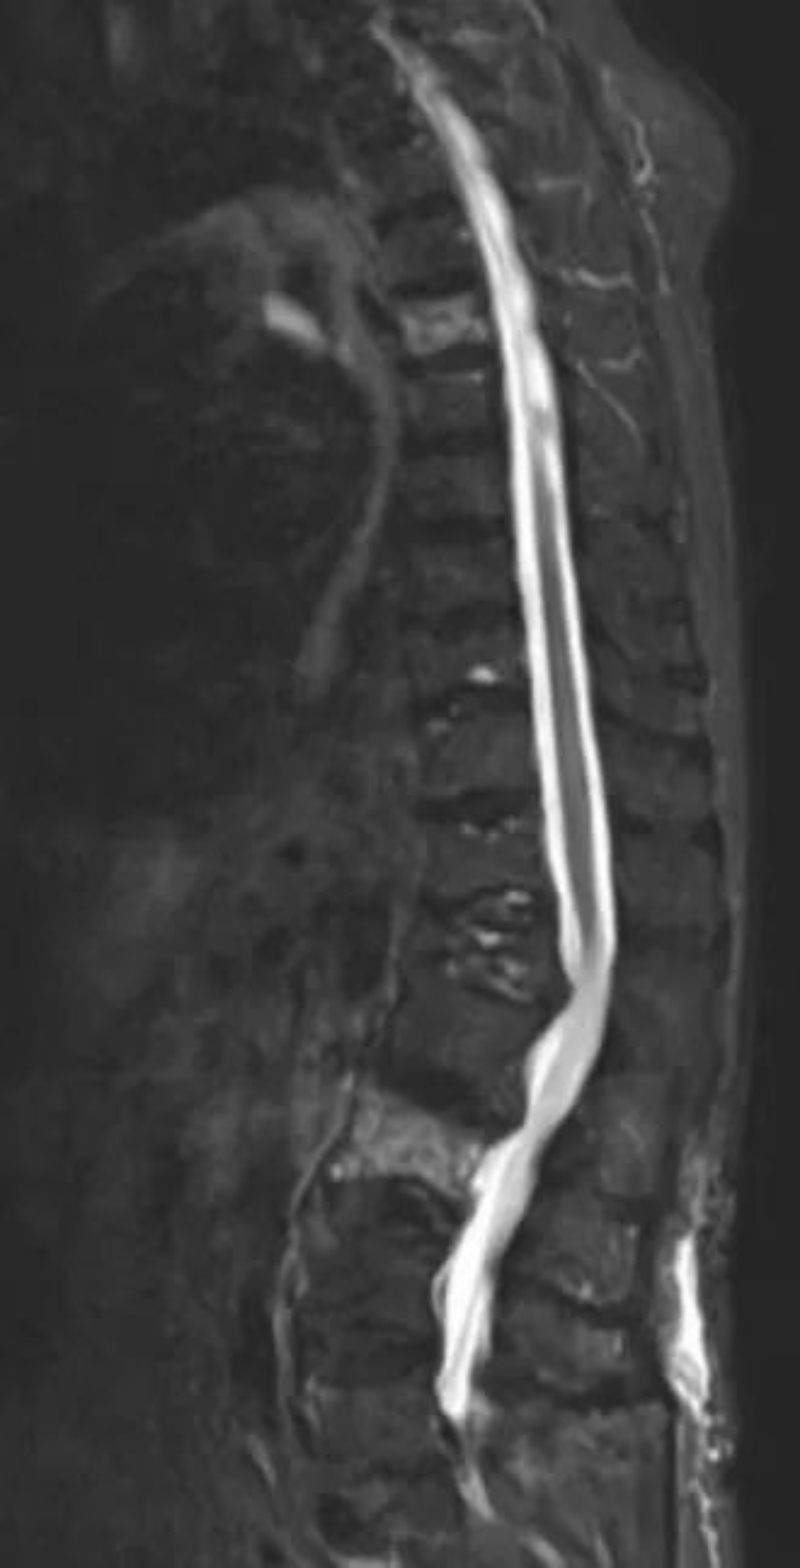

△術前MR可見胸6、腰3椎骨折并骨髓水腫。